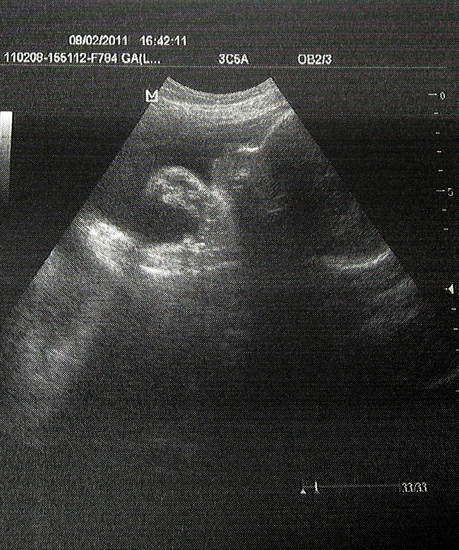

Alle в Образ жизни беременной 15 лет А вот житель нашего пузика))))уже 32 недельки и 5 дней..(вчера были на узи) Фоты пузяш Посмотрите еще 20 записей на эту тему Отменить Ответить Василия Ой, ручкой машет :) Растите здоровенькие 14.02.2011 Ответить Alle спасибо большое))) 14.02.2011 Ответить Виктория Лапки сложил )) прелесть! 11.02.2011 Ответить Ольга Большенькие ужеИ я жду не дождусь третьего узи 09.02.2011 Ответить Alle ага большая деловая колбоса)))) спасибо Олюшка 09.02.2011 Ответить Марийка Ой какой большой житель, серьезный :))) Красота :))) 09.02.2011 Ответить Alle ага..очень сурьёзный.. еле поймали еще чтоб нормально фото сделать..очень активный 09.02.2011 Ответить Марийка Классно))) И у нас тоже вертелка та ещё :))) Ждем тоже последего узи :))) Недельки через 3-4 пойдем :)))) Сейчас 28-я пошла :))) 09.02.2011 Ответить Alle а у вас пишет что 30.. у меня тут тоже не прально считает..у меня 32 09.02.2011 Ответить Марийка Во-во :)) Не правильно считает :))) У нас тут разница на 3,5 недели :))) 09.02.2011 Ответить тут нам еще около 5 месяцев)))) наша 30 неделька))) Чаты Беременных Выберите чат: Январята-2026 Февралята-2026 Мартята-2026 Апрелята-2026 Майчата-2026 Июнята-2026 Июлята-2026 Августята-2026